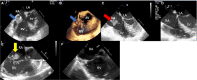

Compared with the extensive data on left-sided infective endocarditis (IE), there is much less published information on the features and management of right-sided IE. Right-sided IE accounts for 5% to 10% of all IE cases, and compared with left-sided IE, it is more often associated with intravenous drug use, intracardiac devices, and central venous catheters, all of which has become more prevalent over the past 20 years. In this manuscript on right-sided IE we provide an up-to-date overview on the epidemiology, etiology, microbiology, potential locations of infection in the right heart, diagnosis, imaging, common complications, management, and prognosis. We present updated information on the treatment of pacemaker and device infections, infected fibrin sheaths that appear to be an easily missed source of infection after central line as well as pacemaker removal. We review current data on the AngioVac percutaneous aspiration device, which can obviate the need for surgery in patients with infected pacemaker leads and fibrin sheaths. We also focused on advanced diagnostic modalities, such as positron emission tomography/computed tomography. All of these are supported by specific case examples with detailed echocardiographic imaging from our experience.